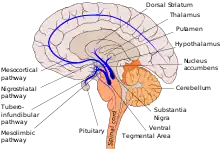

Dopaminergic pathways (dopamine pathways, dopaminergic projections) in the human brain are involved in both physiological and behavioral processes including movement, cognition, executive functions, reward, motivation, and neuroendocrine control.[1] Each pathway is a set of projection neurons, consisting of individual dopaminergic neurons.

The four major dopaminergic pathways are the mesolimbic pathway, the mesocortical pathway, the nigrostriatal pathway, and the tuberoinfundibular pathway. The mesolimbic pathway and the mesocortical pathway form the mesocorticolimbic system. Two other dopaminergic pathways to be considered are the hypothalamospinal tract and the incertohypothalamic pathway.

Pathways

Major

Six of the dopaminergic pathways are listed below.[5][6][7]